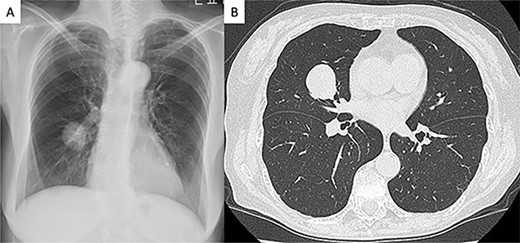

A 75-year-old female patient without any symptoms was referred to our hospital due to an abnormal shadow detected by chest X-ray. Laboratory test results, including tumor markers, were all normal. It had at first been detected 3 years earlier and since the tumor was well demarcated, it was suspected to be a benign lesion such as hamartoma, and the patient underwent a conservative follow-up (Fig. 1A). The tumor size gradually increased on during follow-up and subsequently reached from 20 to 28 mm 3 years after the initial imaging (Fig. 1B). Computed tomography scans revealed a well-circumscribed nodule measuring 28 mm between S4 and S5 in the right middle lobe. Other tests, including serum tumor markers, were within normal limits. We recommended preoperative 18F-fluoro-deoxy-glucose positron emission tomography and bronchoscopy, but the patient refused to undergo preoperative examinations.

Radiologic findings (A) Chest radiograph showed a round mass in the right middle lung field. (B) Computed tomography image showing a 28-mm nodule in the middle lobe of the right lung.